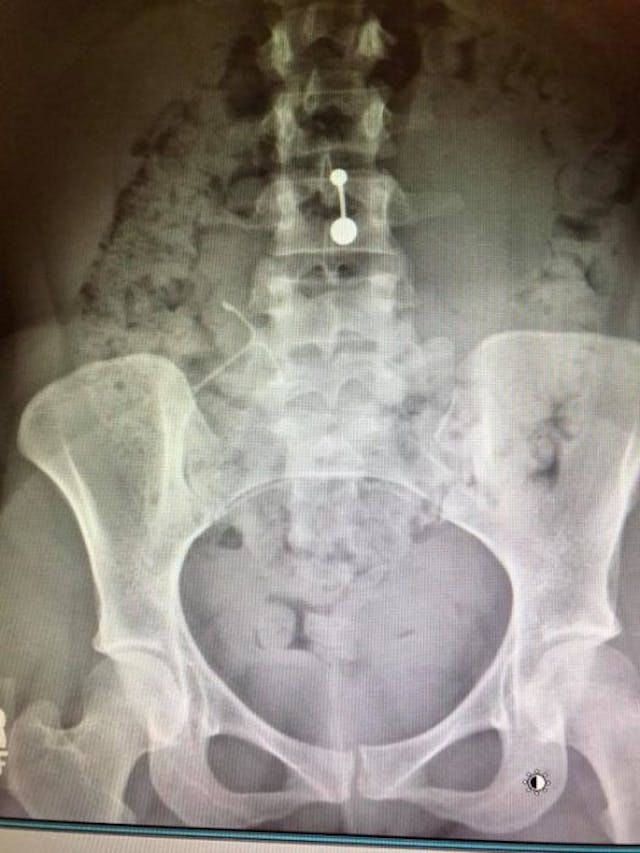

“At the hospital, I got an X-ray that told a very different story from my October ultrasound,” she said. “My IUD was in there, alright: It was wedged into the wall of my stomach. My doctors didn’t say whether they’d ever seen this happen before.”

Smith was referred to an OB/GYN who specializes in IUDs over a week later, who told her that there were two possible causes – the IUD was put in too soon after childbirth, or the tightening of her muscles during her menstrual period has pushed the IUD up. One thing was certain: Smith would need surgery to remove the IUD.